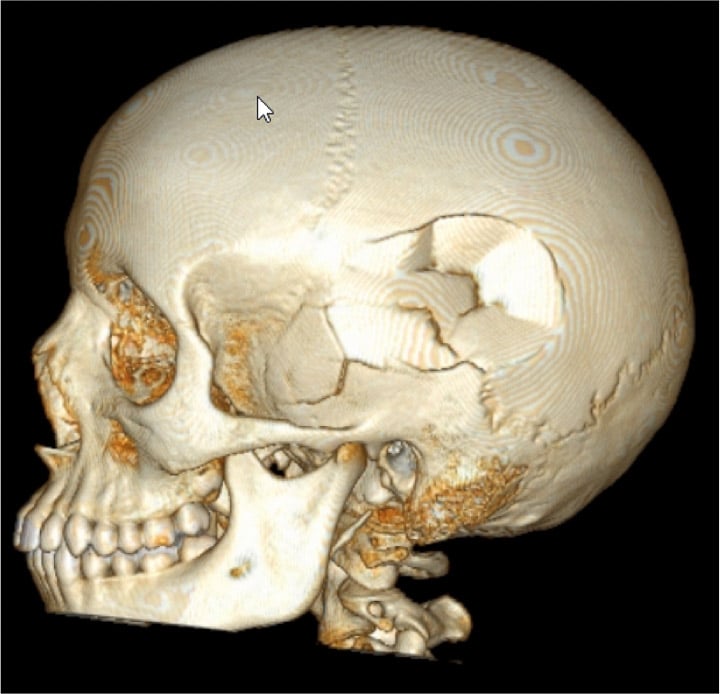

- Acute conditions including infection, trauma

- Brain and spine tumors